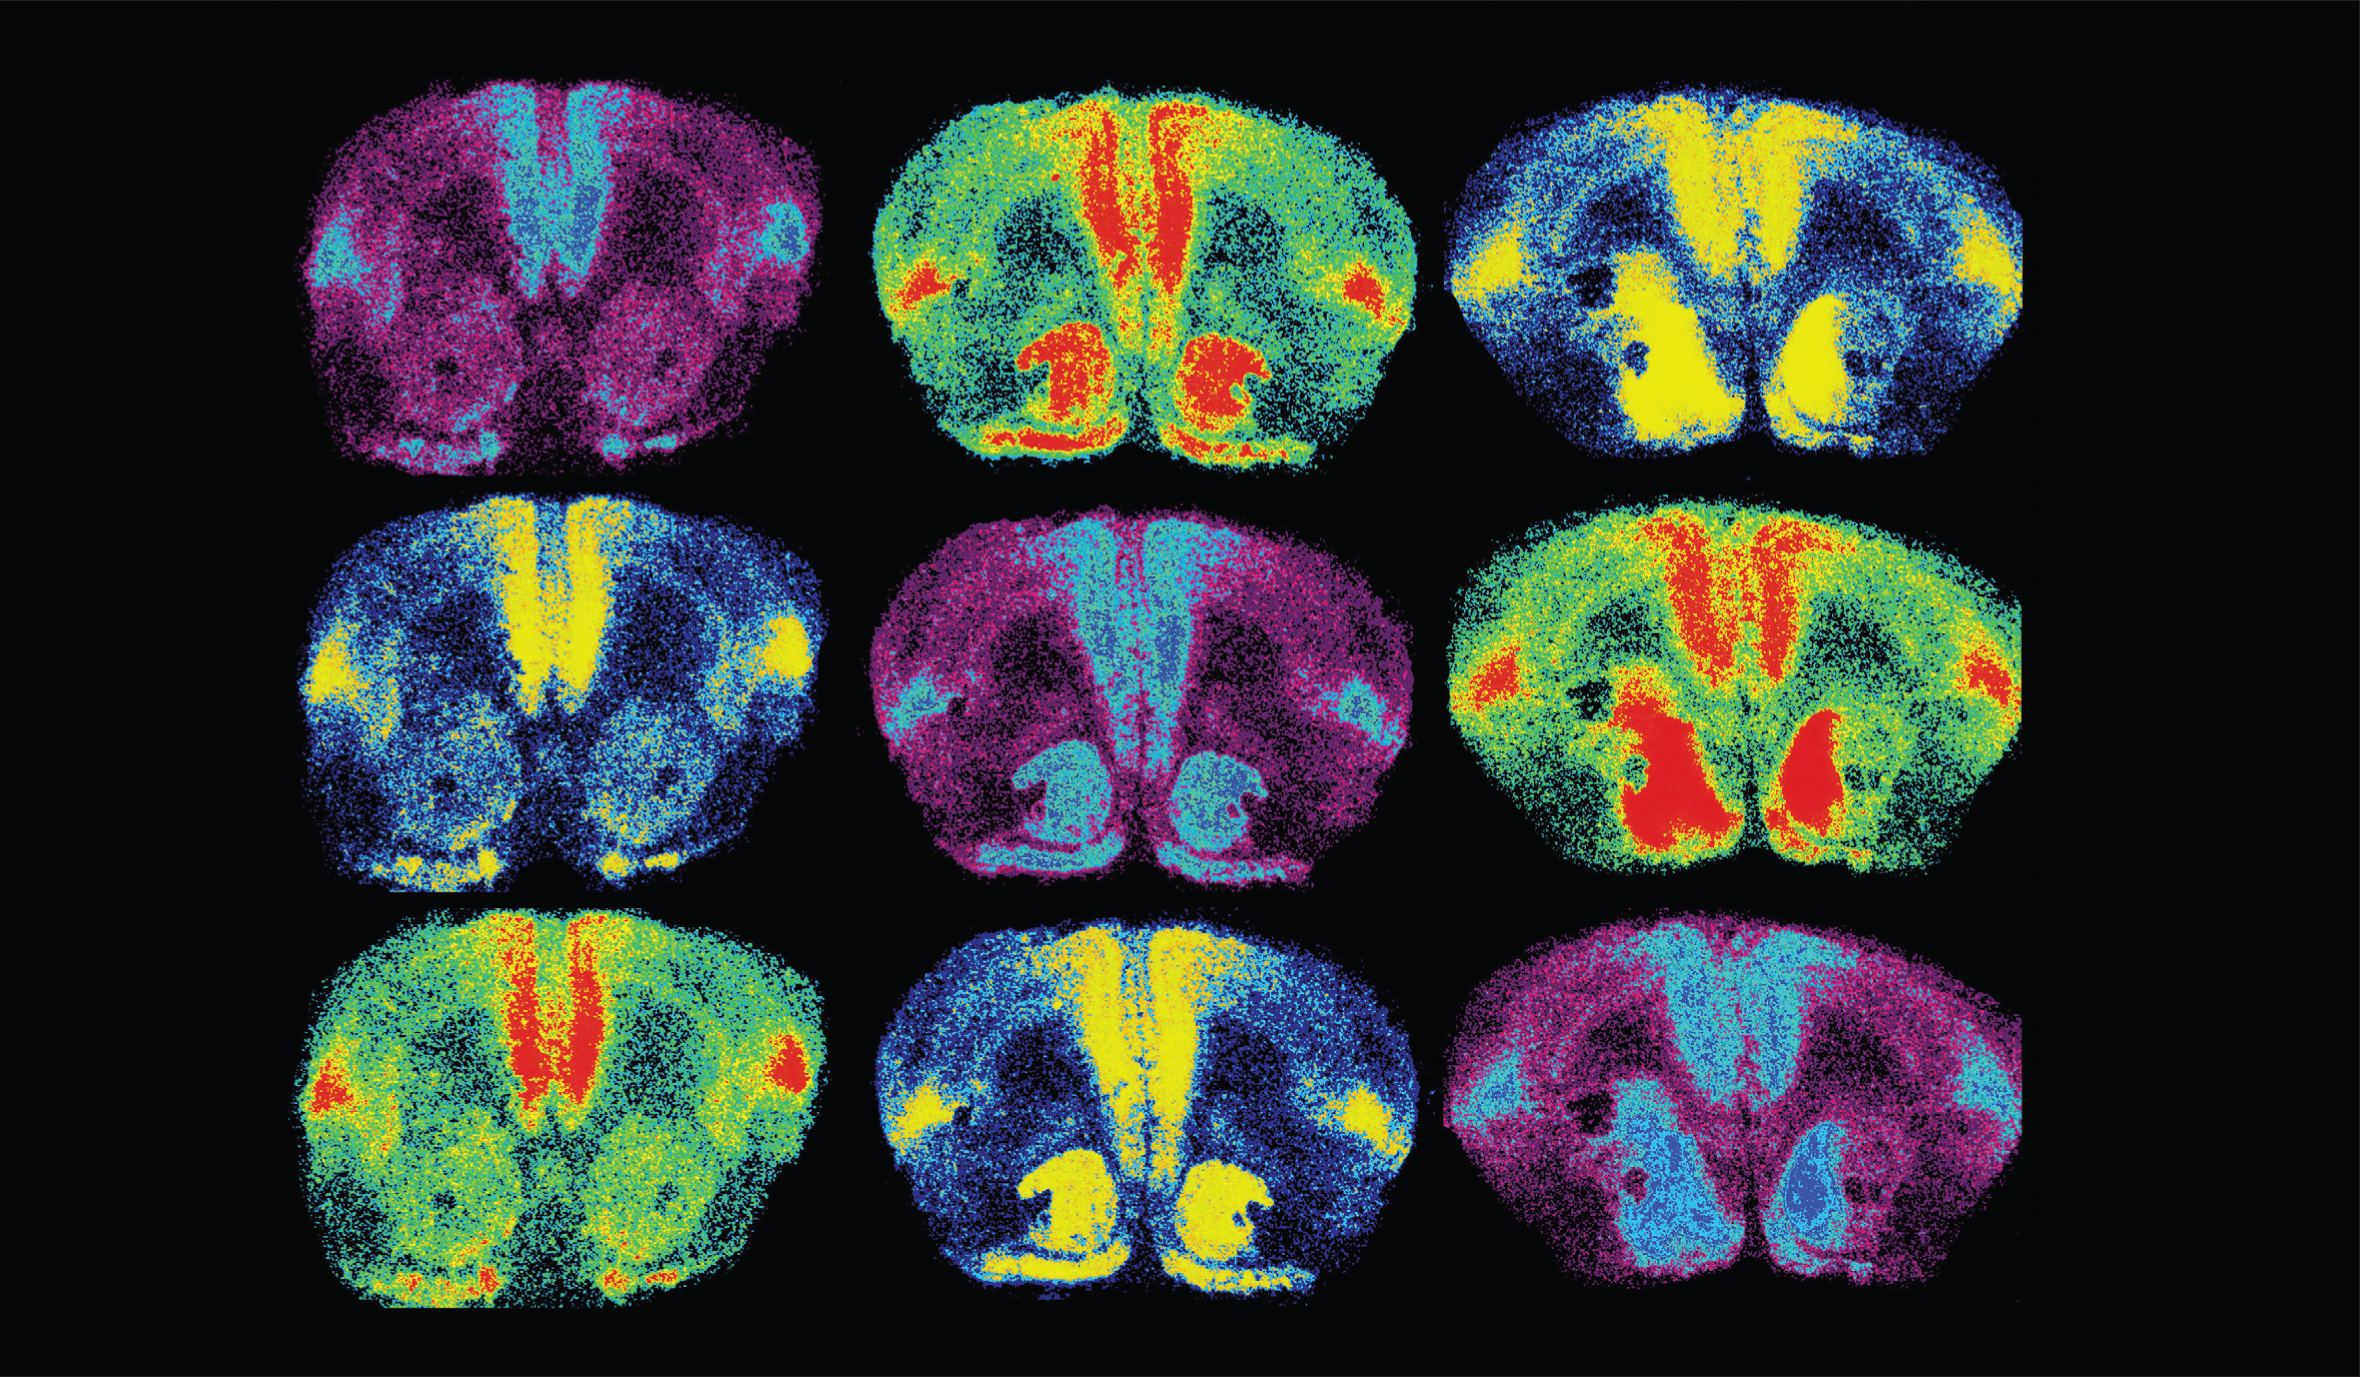

Ross, et al. The Journal of Neuroscience, 2009.

Oxytocin is a brain chemical closely associated with love. In order to study something as unique as love, researchers look at the brains of prairie voles, which mate for life. In this image, oxytocin receptors are labeled in light blue, red, and yellow. When researchers increased oxytocin receptor levels in the brain (right column), they found female voles formed partner preferences faster.